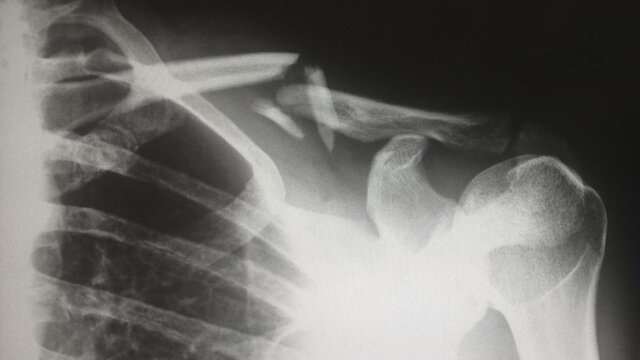

• clasificación de las lesiones deportivas

clasificación de las lesiones deportivas

cuando se origina una lesión se ocasiona un sangrado interno el cual puede ser de dos tipos:

+intramuscular

+intermuscular

• lesiones musculares extrínsecas

lesiones musculares extrínsecas

se generan principalmente en extremidades inferiores. en este tipo de lesión las fibras son comprimidas, provocando la destrucción de un amplio número de ellas y la producción de un hematoma. A menudo, las fascias que envuelven los músculos también llegan a romperse. El dolor es minimo al momento del impacto pero con el tiempo puede provocar dolor, hematomas y limitación de movimiento.